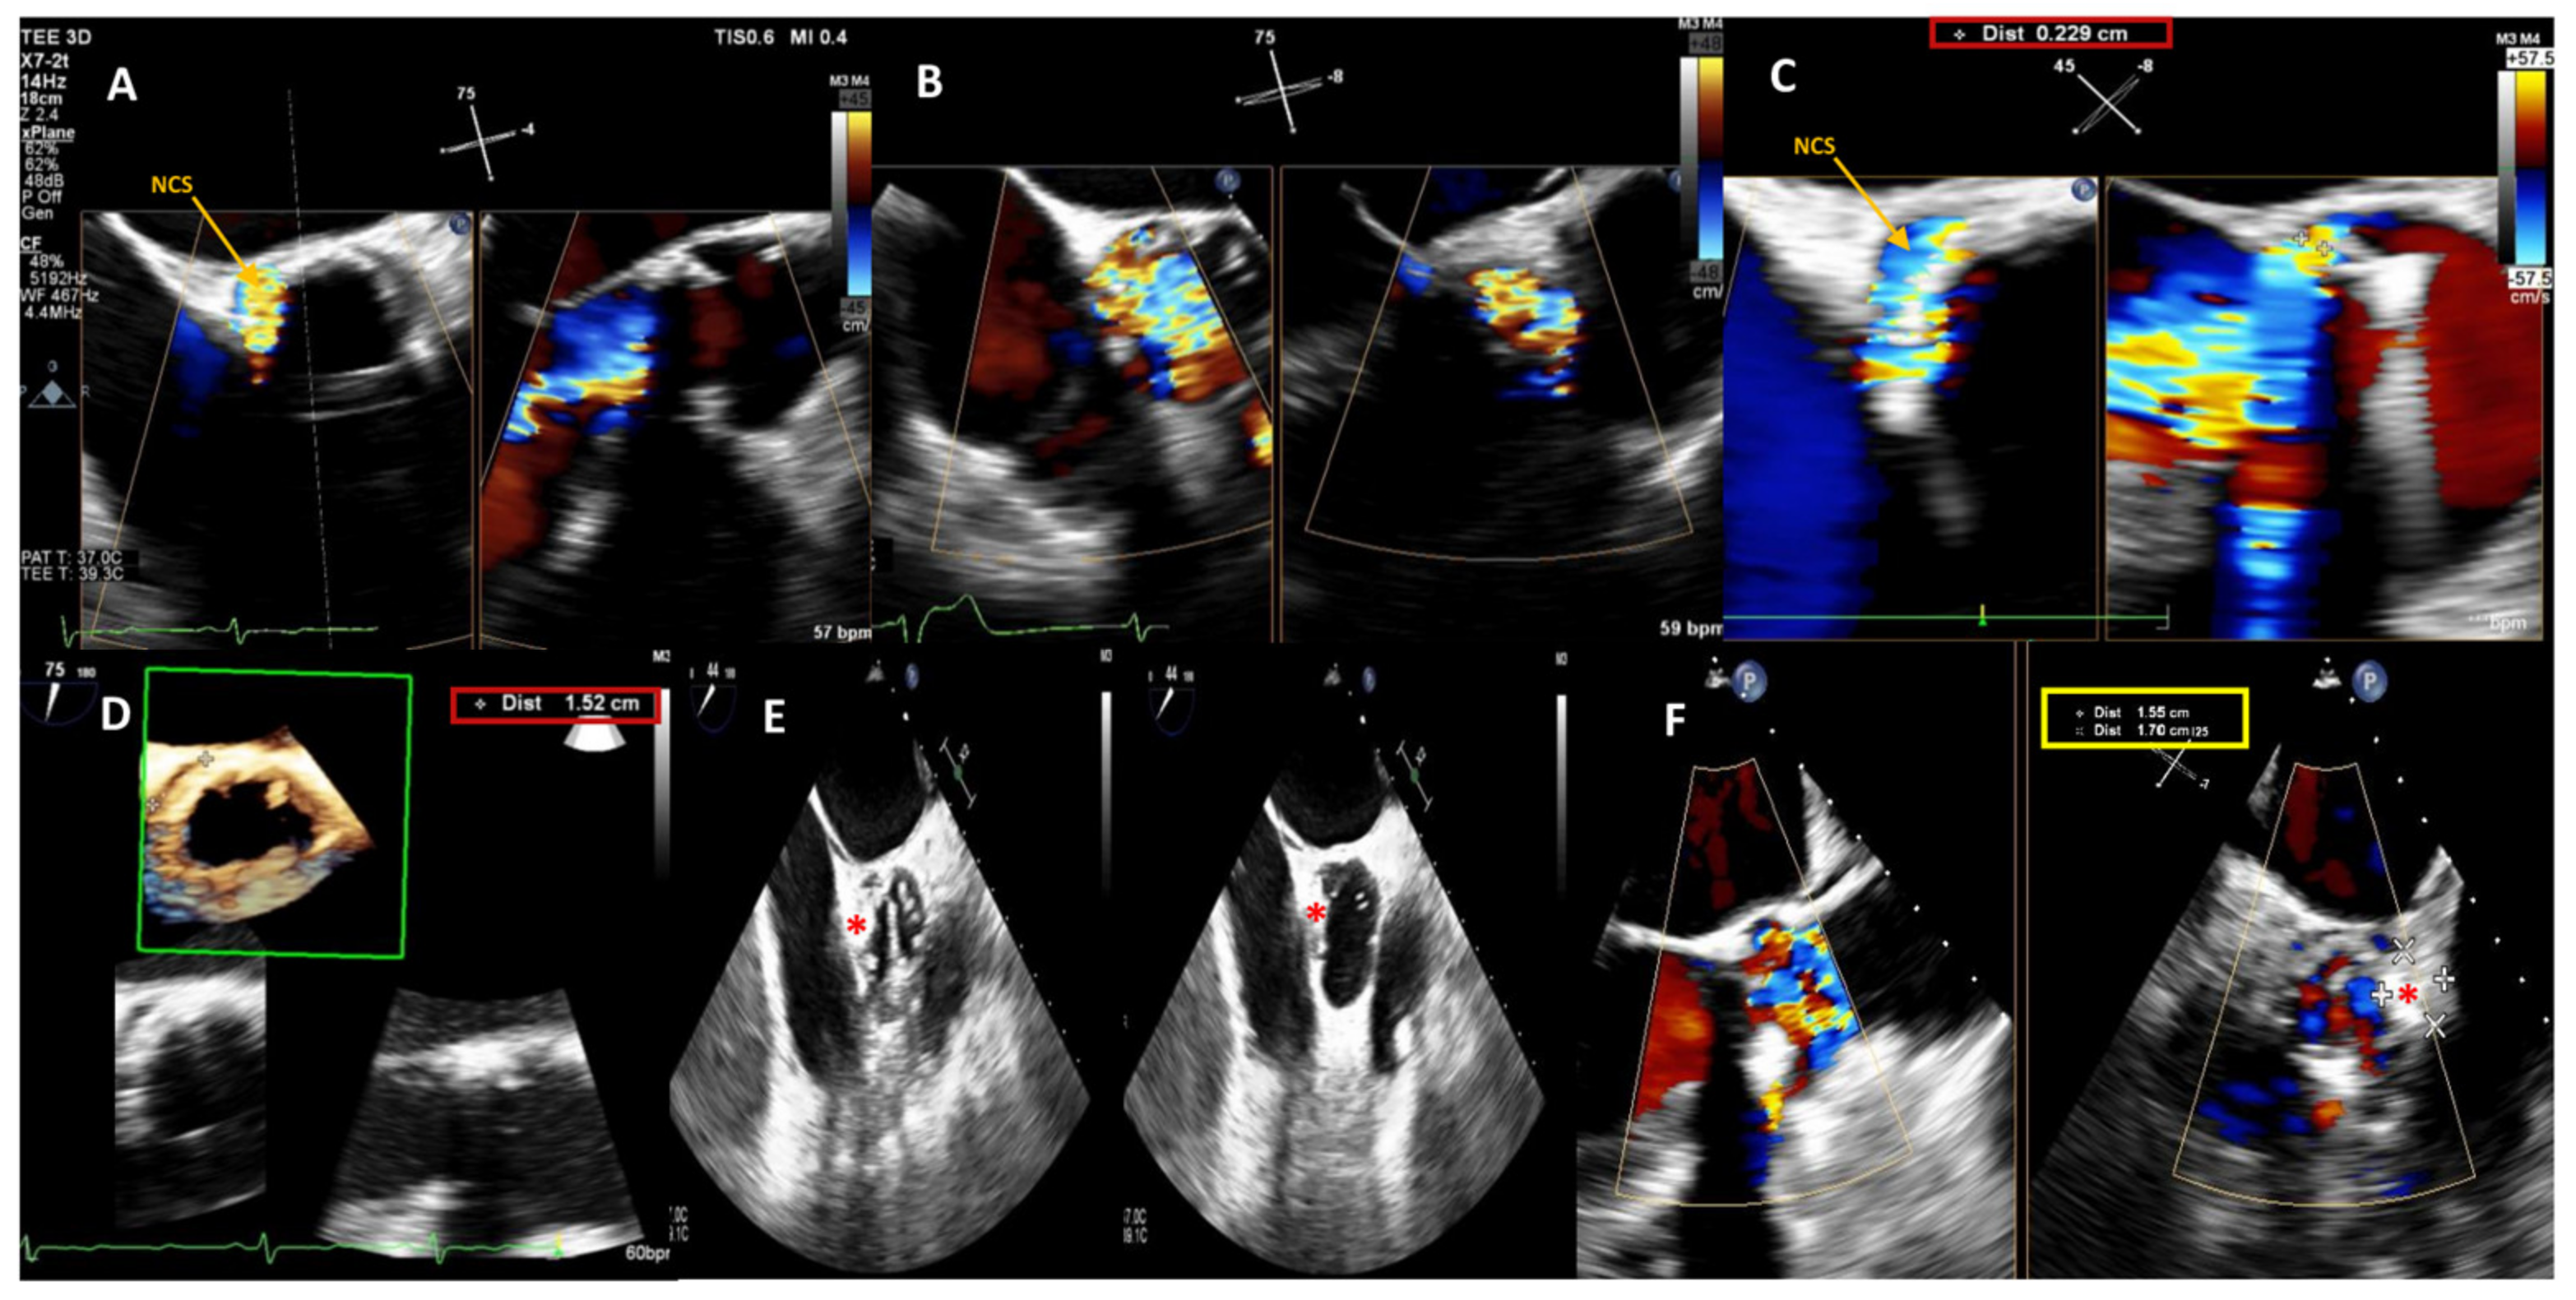

Figure 1.

Baseline 2D/3D Transesophageal Echocardiogram (TEE) color Doppler showing a 15 × 2.3 mm large crescent-shaped NCS paravalvular leak with severe regurgitant jet (A–C) and 3D TEE color Doppler showing the PVL dimensions and location (D). Post-procedure 2D TEE color Doppler showing the correct position of the device (red star) during the cardiac cycle (diastolic and systolic frames, respectively) (E) and confirming stability of the 14 × 6 mm rectangular waist PLD (red star) without impingement on the mechanical prosthetic aortic valve (F). NCS, non-coronary sinus; PLD, Occlutech Paravalvular Leak device.